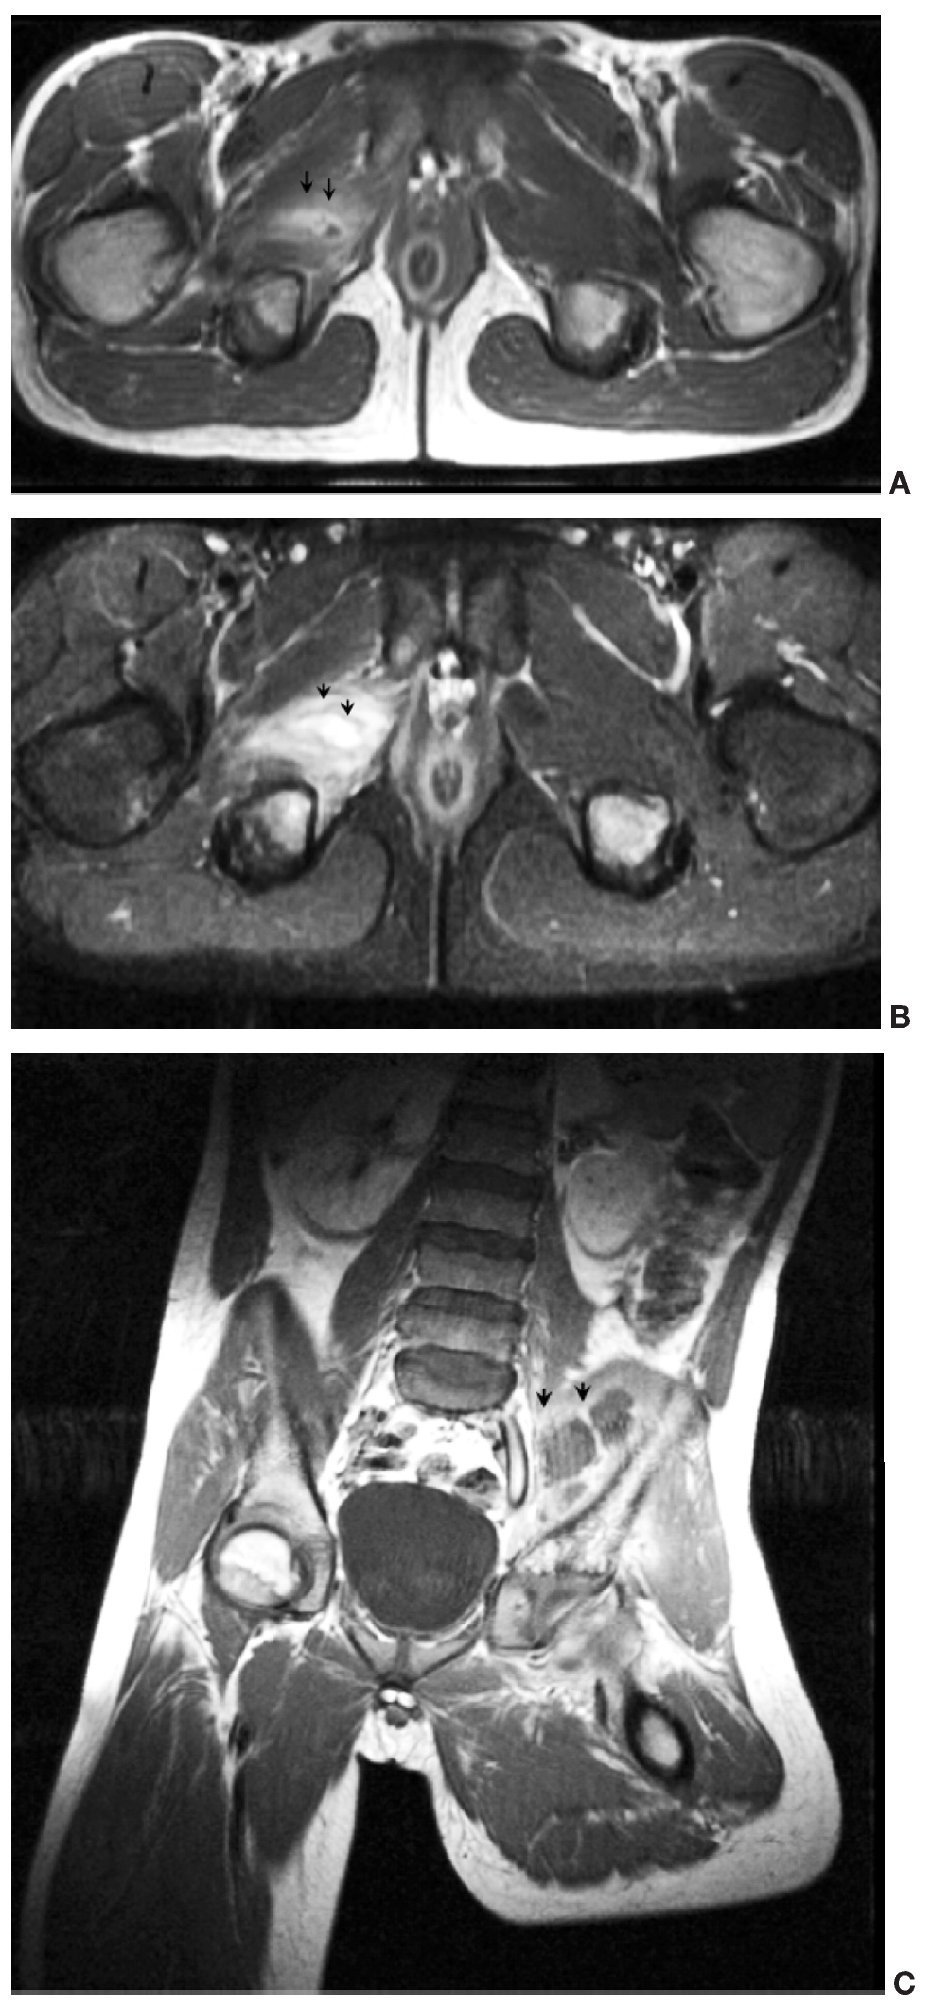

La tabla 3 muestra los hallazgos radiológicos. La radiología simple realizada a todos los pacientes resultó inespecífica; de los 8 casos a los que se realizó ecografía articular sólo dos fueron positivas, encontrando hallazgos inespecíficos (aumento de tejido celular subcutáneo y derrame articular). La gammagrafía ósea vascular realizada a 9 pacientes mostró focos de captación en 4 de ellos. La RM identificó la musculatura afectada, la presencia de abscesos y la afectación ósea subyacente. Las secuencias STIR en RM mostraron la musculatura afectada como zonas de hiperseñal (fig. 1). En secuencias espín eco la musculatura afectada presentaba un aumento de tamaño, con una disminución difusa de la señal en secuencias potenciadas en T1 y un aumento de señal en secuencias T2. En estadios precoces no existían colecciones focales de líquido, y tras la administración de contraste endovenoso existía realce heterogéneo.

Fig. 1. Secuencia STIR que muestra la hiperseñal del músculo psoas ilíaco y mínimo derrame articular en la articulación sacro-ilíaca derecha.